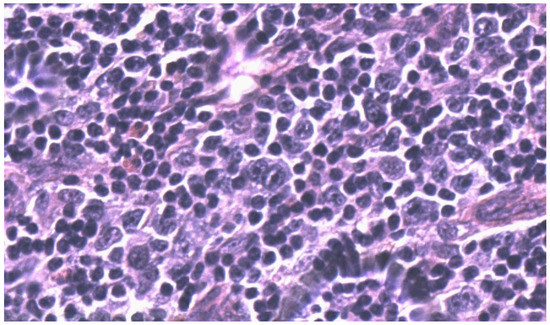

2. Case Report